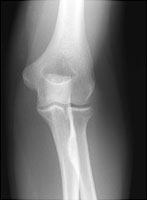

- Click on the image for a larger versionBAP radiograph of the elbow. This demonstrates the subtle fracture of the radial head.